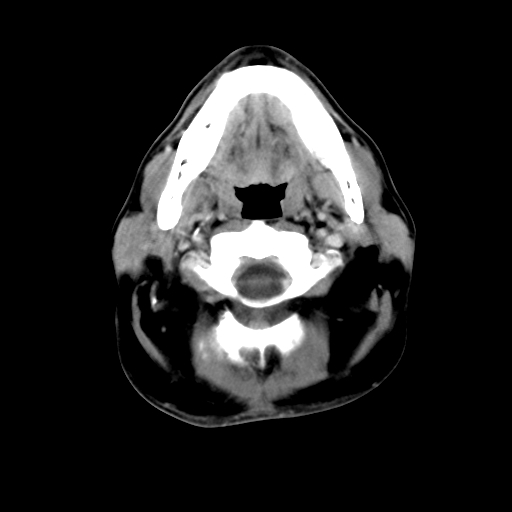

标题: CT24019:男,45岁,发现颈部肿物5个月。 [打印本页]

标题: CT24019:男,45岁,发现颈部肿物5个月。

男,45岁,发现颈部肿物5个月,彩超示:双侧颈部及下颌部软组织增厚。

考虑双侧颈项部良性对称性脂肪增多症。

双侧颈项部脂肪沉积